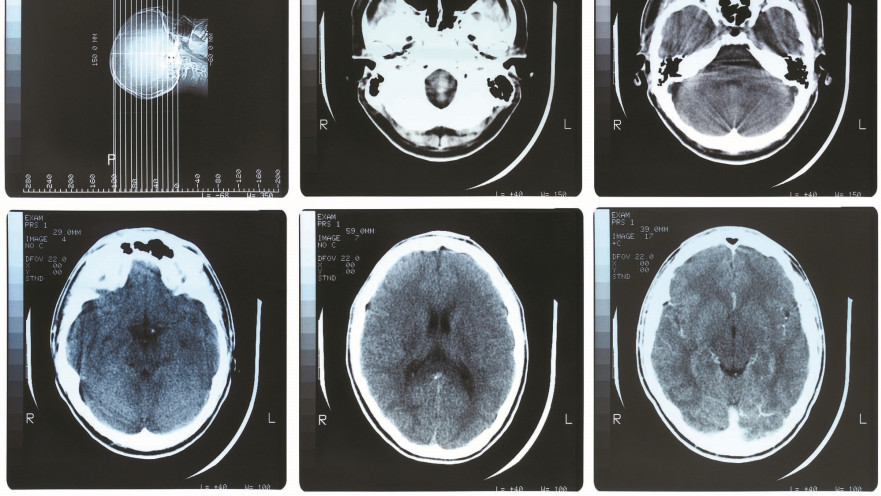

חלקיקי זיהום אוויר במוח

חלקיקי זיהום אוויר במוח | צילום: אינגאימג